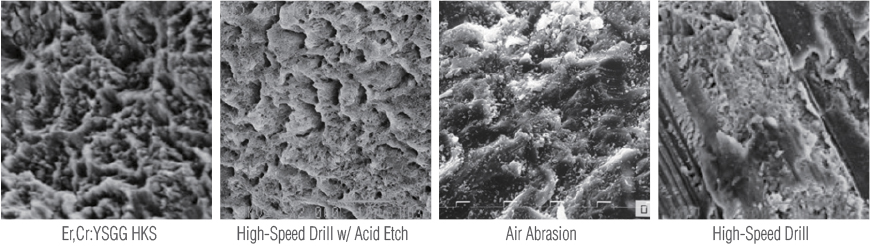

Cross-sectional Comparison under Scanning Electron Microscope (×1000 Magnification)

Cavity Prep., Veneer Prep., Crown Removal, Resin Filling

- Enlarged surface area at the treatment site ensures excellent bonding strength

- Minimal risk of secondary caries due to microcracks

Surface Preparation Comparison